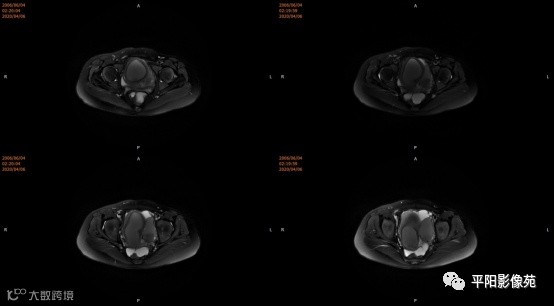

子宫10cm×12cm大小,饱满,呈紫红色,子宫下段增粗膨大呈柱状,右侧卵巢可见一约18*15cm大小的肿物,表面呈紫红色,输卵管明显增粗膨大,伞端及卵巢粘连包裹于子宫后壁及侧盆壁,左侧卵巢可见一约8*7cm大小的囊肿,左侧输卵管增粗膨大伞端包裹粘连于子宫后壁及侧盆壁,直肠粘膜粘连于子宫后壁。部分大网膜粘连于子宫及卵巢表面。 注射器针头刺入子宫肌层至宫腔,抽取出大量暗红色血液,宫腔内积血,子宫缩小,子宫下段膨大,不排除生殖道畸形,双侧卵巢巧克力囊肿可能,钝性分离粘连,针头刺入右侧卵巢囊腔,吸出咖色液体约800ml,娩出右侧卵巢,切开右侧卵巢囊肿表面组织达囊壁,钝性剥离囊肿,剥离过程中可见大量黑褐色液体流出,3-0可吸收线缝合囊腔止血使卵巢成形,大小约5*6cm,同法处理左侧,使左卵巢成形,分离双侧输卵管粘连,暴露伞端,行宫腔穿刺可抽取出大量暗红色血液,考虑生殖道畸形,需改阴式手术探查,破坏处女膜,术中向患者家属交待病情,需改阴式手术破坏处女膜,患者家属表示理解,同意改阴式探查并签字。 患者取膀胱截石位,常规消毒铺巾,见外阴外观发育正常,分开小阴唇,见尿道口下方可见处女膜环,剪开处女膜环,可见阴道壁约1cm,前为盲端,分开处女膜后,于尿道下方阴道口位置,将1:10000的肾上腺素注入阴道直肠间隙,在尿道口下方阴道壁痕迹处横切约2.5cm,钝性分离,可及一囊肿,表面淡紫色,20ml注射器经此处穿刺,抽出暗褐色积血,用注射器向阴道积血方向穿刺,抽出褐色积血,探查囊腔与宫腔相通,未见明显宫颈组织,上段未见阴道粘膜,考虑宫颈缺如及生殖道畸形,清理宫腔积血,将子宫下段最低端缝合于约1cm的阴道粘膜上,形成宫颈形状,宫腔放置一根引流管,查无出血。

无痛宫腔镜检查:可见手术缝扎线,未见宫颈组织,宫腔形态失常,可见子宫内膜,未见明显双侧输卵管开口。

宫颈缺如、阴道闭锁

4.MRI检查 对软组织分辨率好,能够清晰区分子宫及阴道,对子宫内膜、结合带、肌层可清晰分辨;能明确子宫、宫颈、阴道结构异常的部位、范围、性质等。宫腔内经血潴留时,宫腔内见短T1长T2信号。